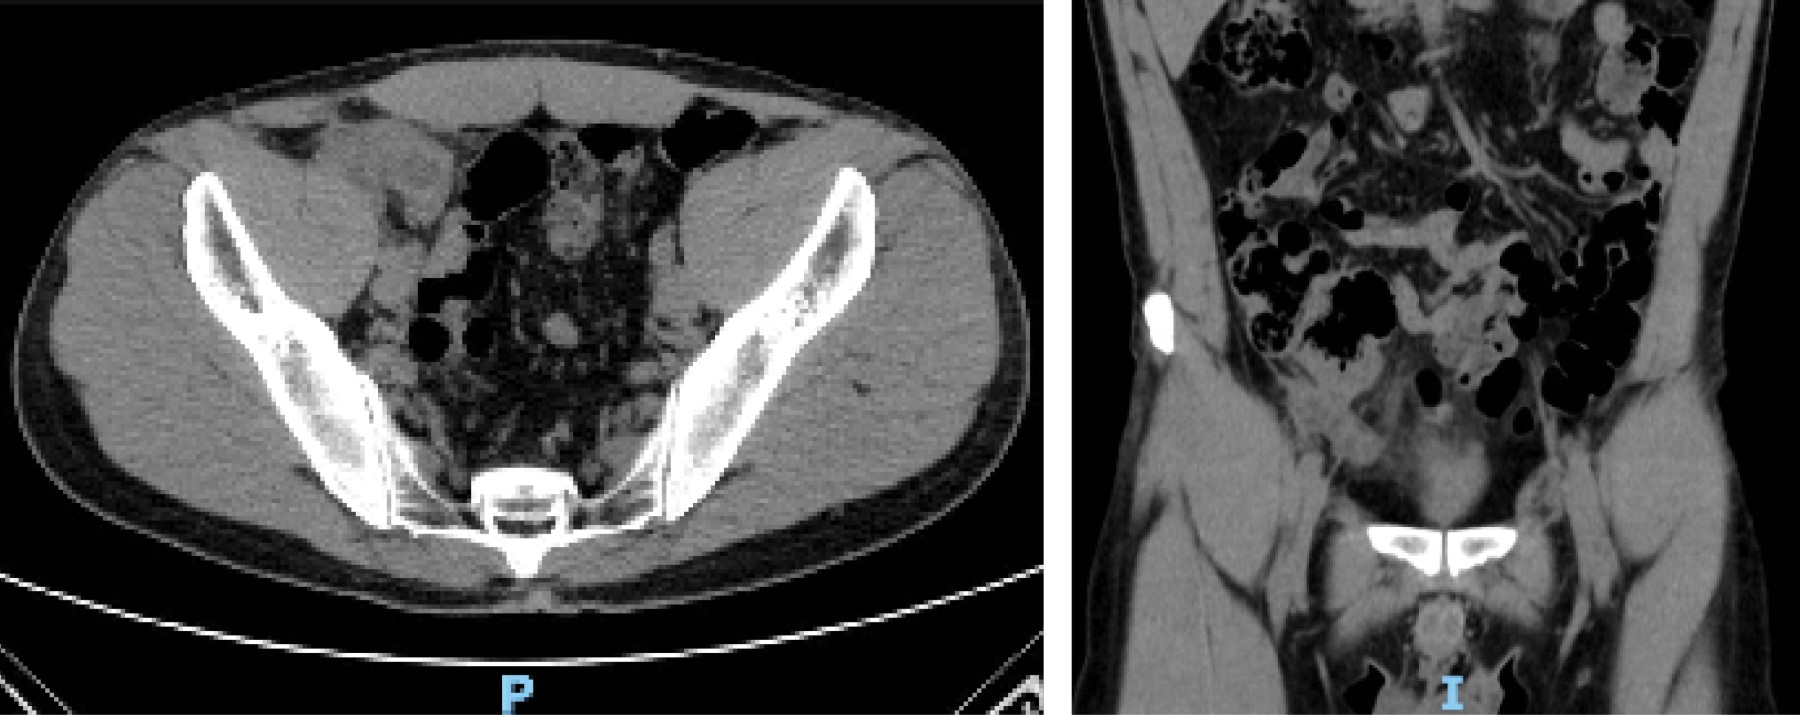

Introduction: appendicular neoplasms represent 1% of all colorectal cancers, one of the histological variants is appendiceal mucinous neoplasm, formerly known as mucocele. The clinical presentation is largely similar to that of acute appendicitis, so its preoperative diagnosis is rare. Clinically, patients present different symptomatology depending on the stage they are in, the most common manifestations are pain in the right iliac fossa, fever, palpable mass, abdominal distension, weight loss, anemia, chronic abdominal pain, infertility, among others. The defining pathologic characteristic of evidence of low-grade appendiceal mucinous neoplasm (LAMN) is invasion of the appendiceal wall, the presence of irregularity in the wall of the observed and the increase in thickness of the soft tissues can predict the malignancy of the tumor. Peritoneal involvement at the time of diagnosis can be up to 53%. The possibility of disease progression to pseudomyxoma peritoneal exists if dissemination occurs by rupture of the lesion and release of mucin into the peritoneal cavity. The treatment of LAMN always requires surgical management and the use of hyperthermic intraoperative chemotherapy in case of peritoneal involvement is still under debate. Case presentation: this case deals with a patient, 41 years old, who after three months with abdominal pain in the right iliac fossa, is taken to the operating room for a diagnostic laparoscopy due to the suspicion of a mucinous neoplasm, no mucinous lesions were found, an appendectomy plus cecectomy was performed. With stapler, pathology reported LAMN with serial involvement (pT4) and at six months a control laparoscopy with no evidence of mucinous lesions. The involvement of the serosa opened the discussion on whether hyperthermic intraperitoneal chemotherapy is necessary when there are no visible mucinous lesions and there was no mucin contamination. Conclusions: the literature to date has no clear evidence on the prognosis of this type of injury and whether it is useful or not. The challenge of this diagnosis will be to have a multicenter prospective study that allows the development of care protocols with strategic treatments.

Figure 1